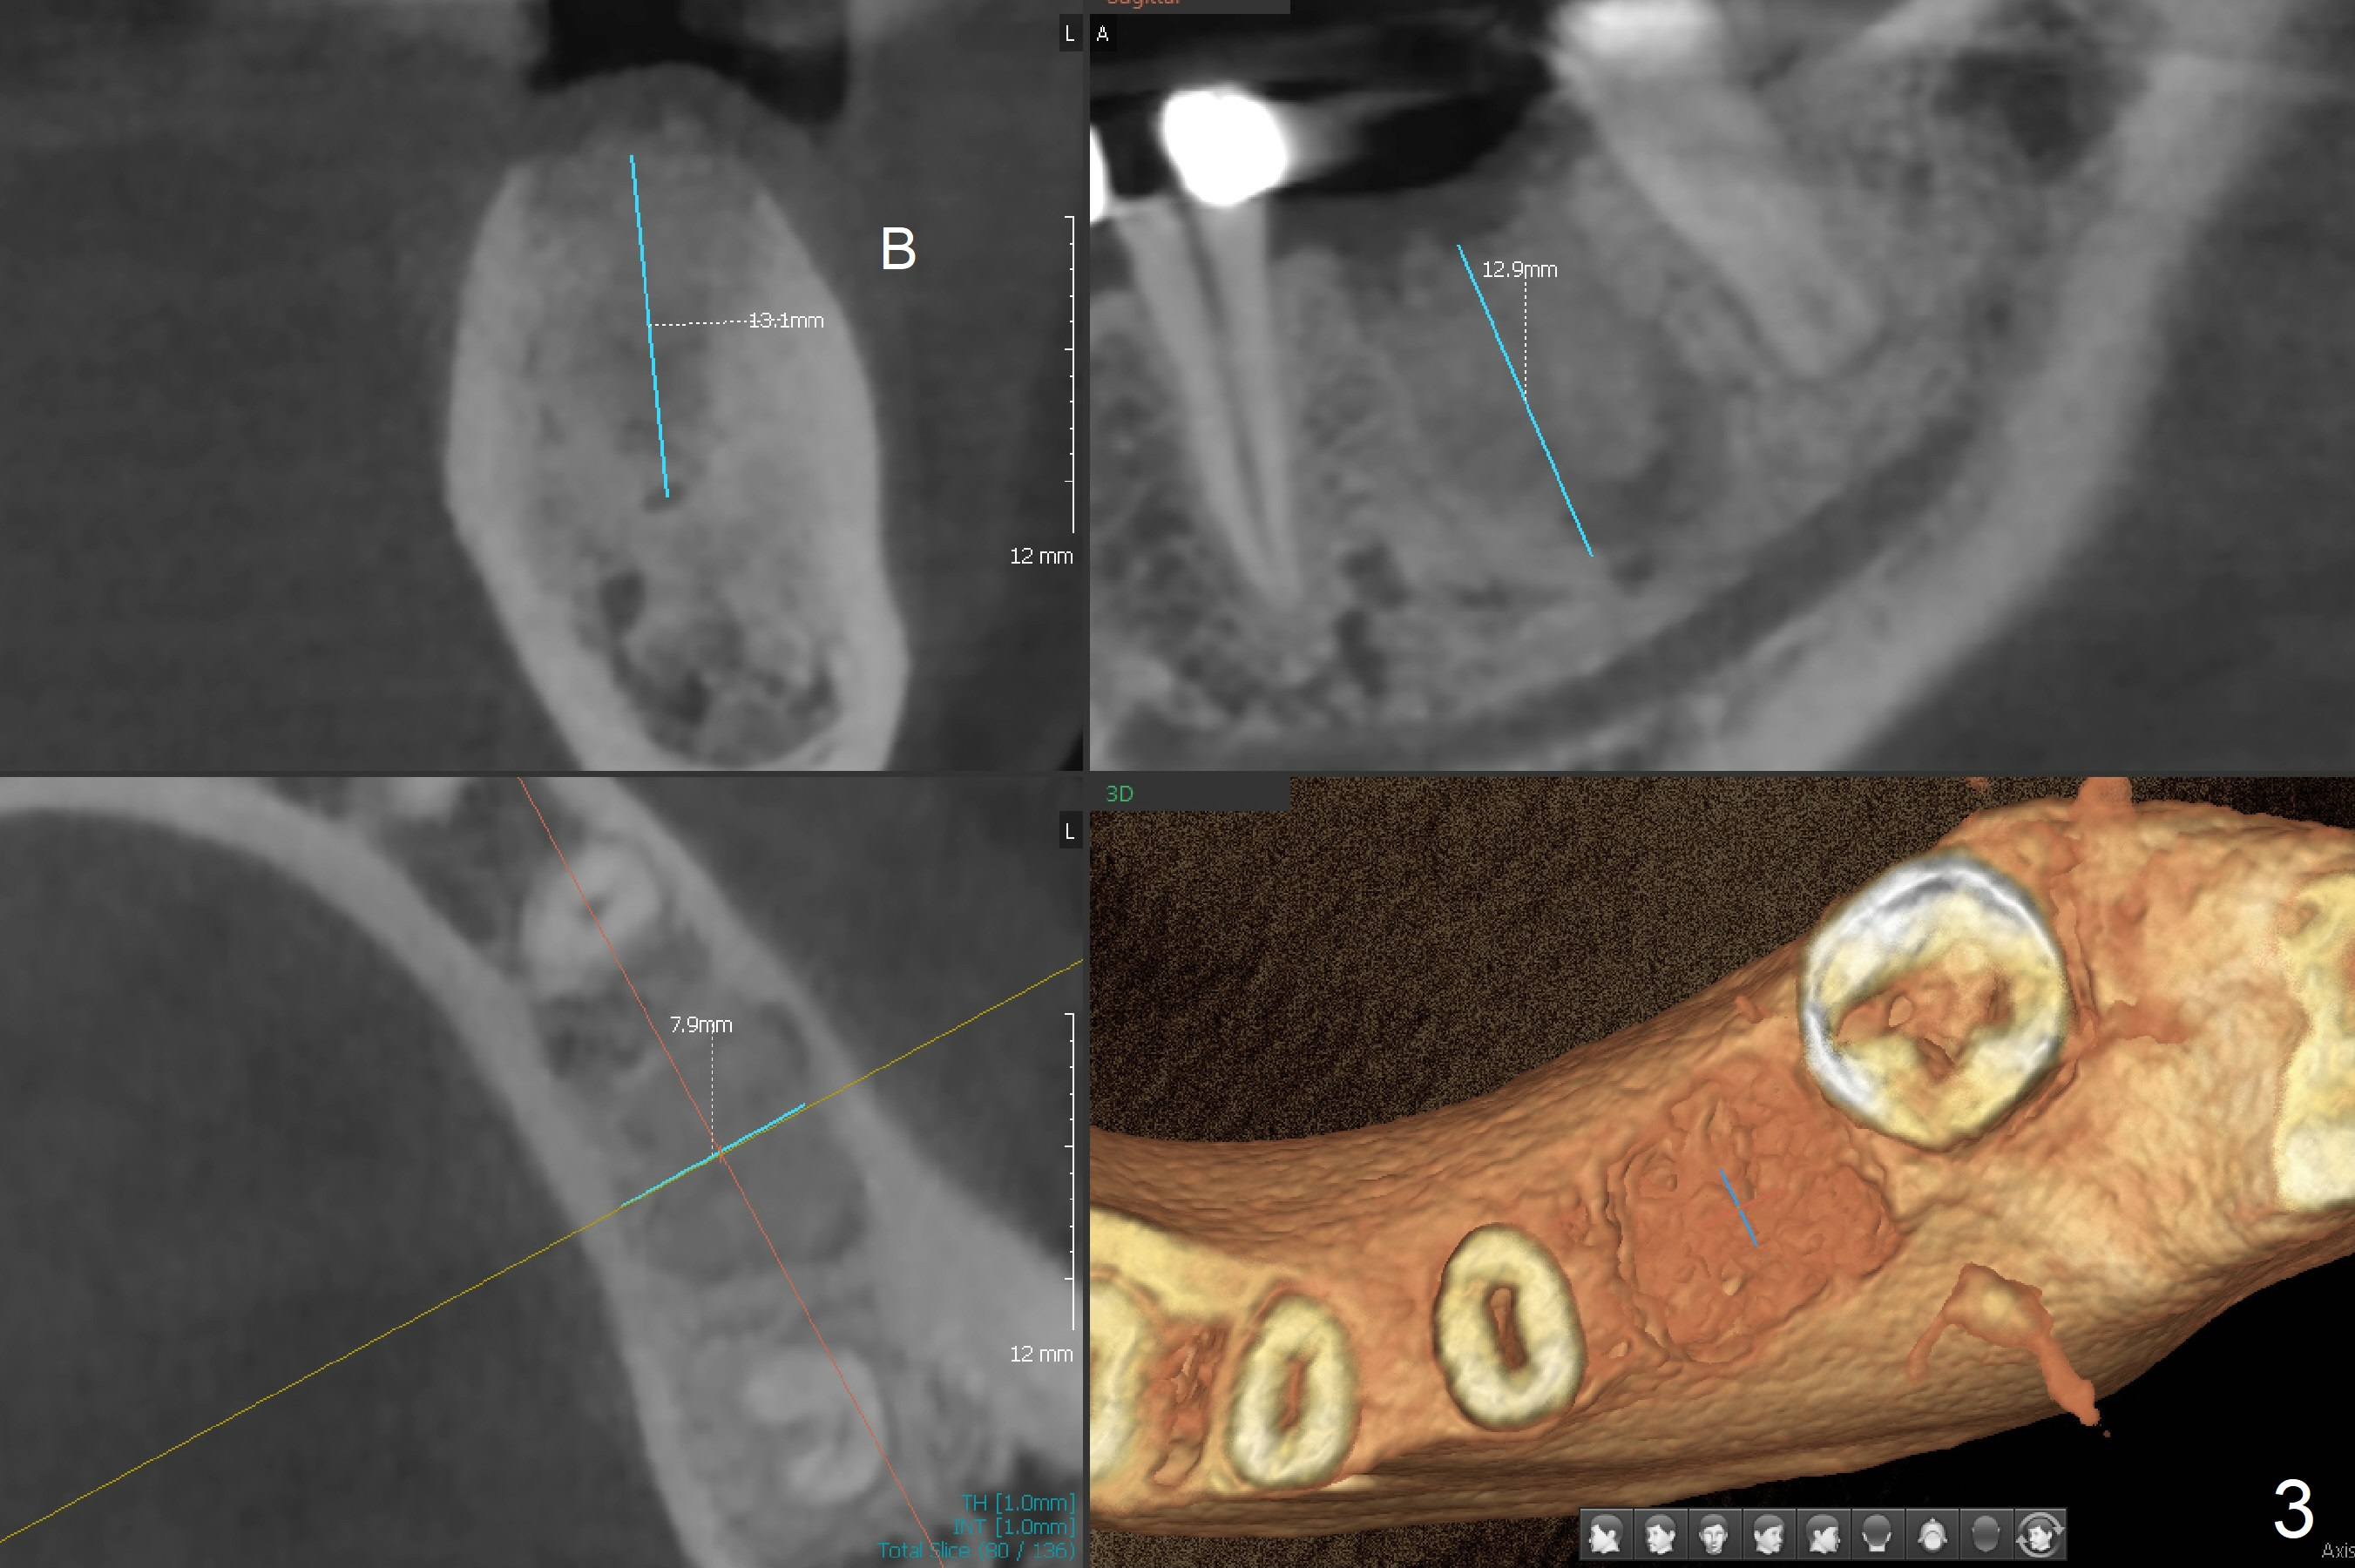

A 53-year-old woman has discomfort at #19 4-5 years post RCT (Fig.1 (*: PARL), 1 year before extraction). She returns for implant placement 4 months post socket preservation in other office (Fig.2 *). The socket appears to have healed with dense bone formation (average 1160 units, Fig.3). A 5x11.5 mm implant will be placed with guide (Fig.4). Will composite at #20 MOL (Fig.2 arrowhead) and PVS impression after CBCT affect surgical guide fabrication accuracy? Or the composite should be done after guided surgery?